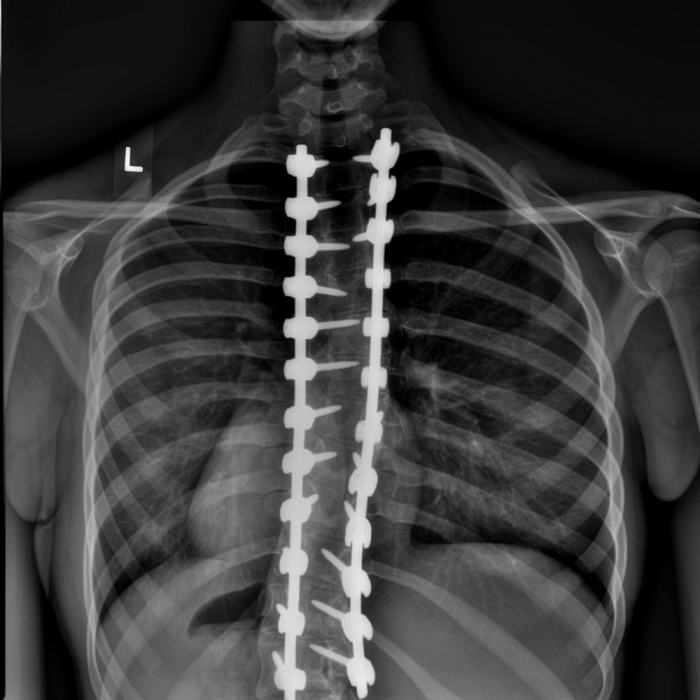

Spinal Fusion for Scoliosis

There are different types of scoliosis surgery. Spinal fusion is the most common type of operation which connects the vertebrae in your spine using metal rods and screws to fuse them together.

Spinal fusion is typically done in one of two ways:

– Posterior fusion: where the rods are attached to your spine directly from behind. This is the most common and widely used approach.

– Anterior fusion: where the rods are attached to your spine from the side of your trunk.

Both procedures have the goal of aligning the spine and holding it in position. Like any surgery, complications may occur. Scoliosis surgery is considered a treatment of last resort.